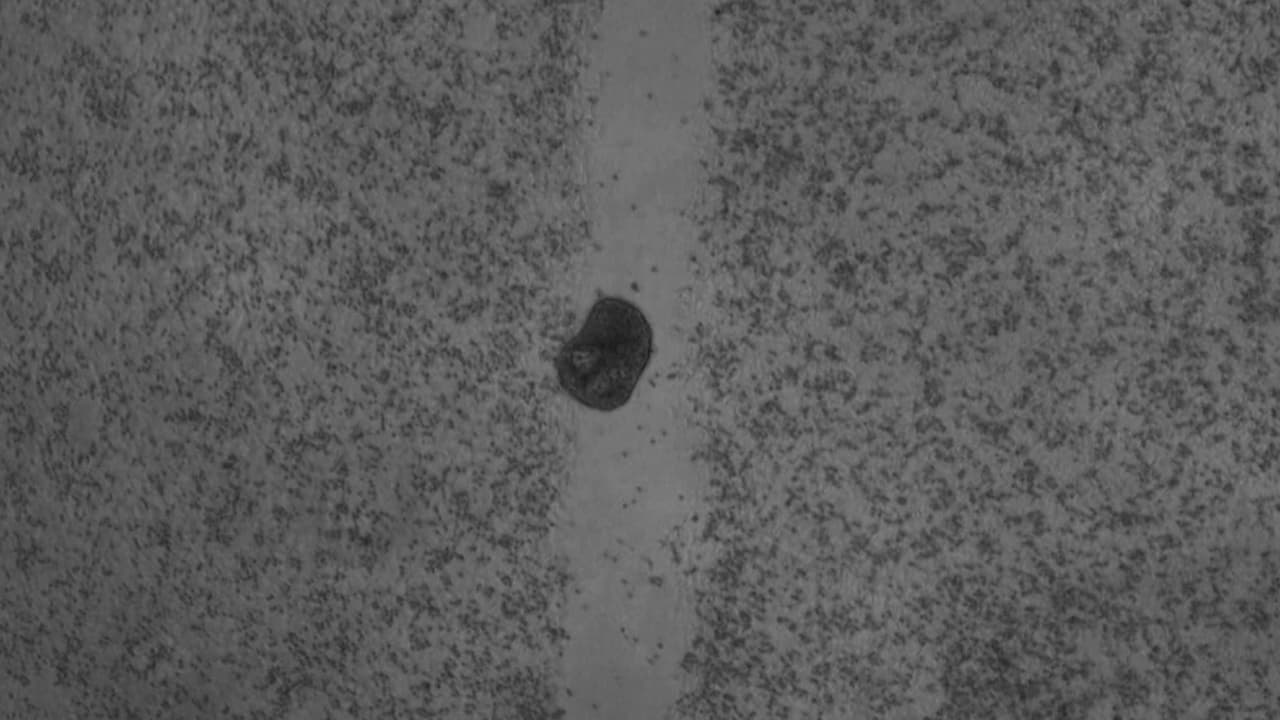

‘Antrobots’, los diminutos robots biológicos creados a partir de células humanas

Un equipo de la Universidad Tufts y del Instituto Wyss de la Universidad de Harvard han bautizado a estas creaciones como ‘Antrobots’ y esperan que puedan ser usados con fines sanitarios. Sigue las últimas noticias en Univision.